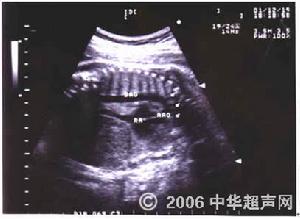

主動脈造影檢查:主動脈造影是確診主動脈弓及其分支畸形最可靠的診斷方法。於升主動脈內插入導管,注入造影劑進行主動脈及其分支造影,雙向電影攝片檢查可顯示主動脈弓及其分支的起源、走向、粗細和其它異常,從而明確診斷。